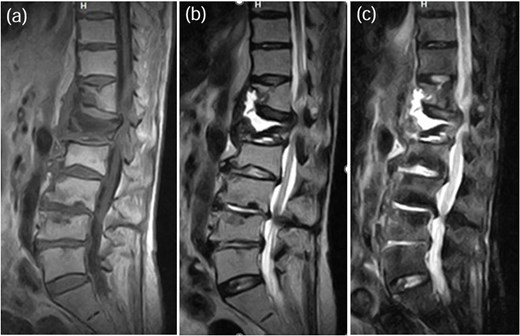

MRI demonstrated signal changes at Th7-Th8, with low intensity on T1-weighted images (a), high intensity on T2-weighted images (b), and no suppression on short-tau inversion recovery (STIR) images (c).